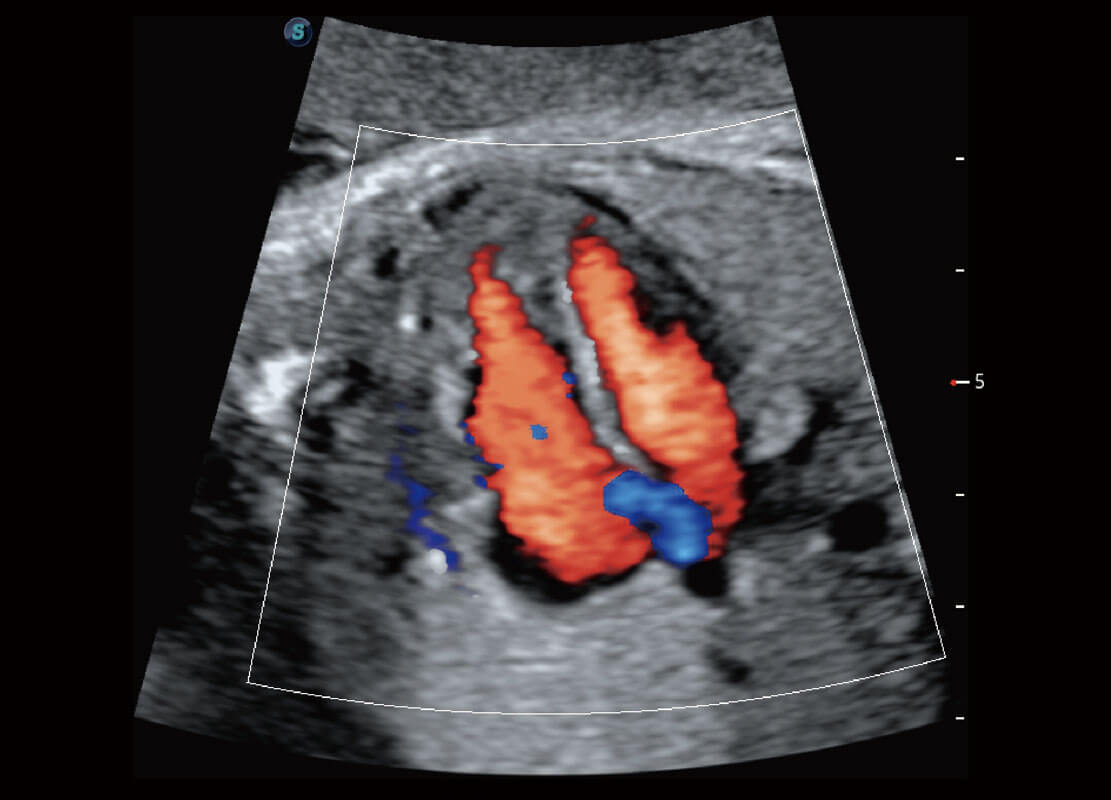

胎儿体循环

P60搭载一系列胎儿心脏成像技术,实现精细的胎儿心脏评估。

四腔心血流

右室双出口